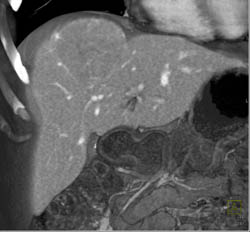

Diagnosis

Focal Nodular Hyperplasia (FNH)